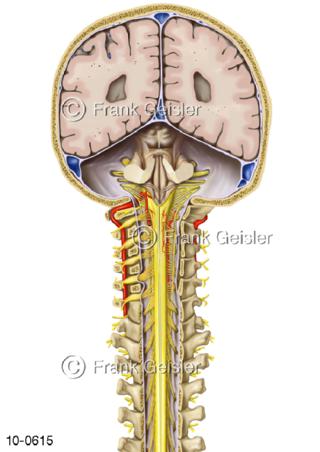

Bildergalerie Nervensystem

Bilder zum Nervensystem,dem Gehirn, Teil des zentralen Nervensystem, Zentralnervensystem ZNSmit Rückenmark, Abbildungen zum Nervengeflecht (Nervenplexus), die Verflechtungen von Nervenfasern, aus der Wirbelsäule hervortretende Nervenäst sowie Nervenzellen der Nerven